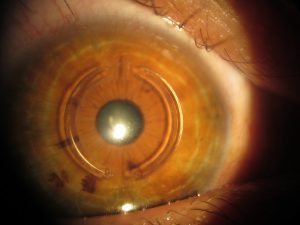

Kornea dokusu içerisinde açılan kanala yerleştirilerek korneal düzleşme ve korneal kalınlaşmaya neden olan PMMA’ dan yapılmış saydam bir aparattır. Özellikle düzensizliğin fazla olduğu keratokonus hastalarında görme artışı sağlamak ve/veya kontakt lens uyumunu arttırmak için kullanılır.

Kornea kalınlığı 5 mm’lik zonda 400µm ve üstünde olan hastalara, Kmax:60D ve altında olan hastalarda uygulanabilir. Keretakonusun durduğu hastalarda tercih edilebileceği gibi Cross-Linking ile birlikte de uygulanabilir.

Korneal halka uygulaması için açılan kanal mutlaka FEMTOSANİYE lazer yardımı ile açılmalıdır. Mekanik yöntemlerle açılan kanallarda başarı düşmekte ve komplikasyon artmaktadır.

Korneal Ring Nasıl Yerleştirilir?

Detaylı göz muayenesini takiben; gözü uygun olan hastalara Femtosaniye lazer yardımı ile topikal (damla) anestezi ile korneal tünel hazırlanır ve PMMA’ dan yapılmış uygun ring kornea içine yerleştirilir.

Başarıyı etkileyen ve komplikasyonları azaltan en önemli etken gözün için uygun olması ve mutlaka Femtosaniye lazer yardımı ile yerleştirilmesidir.